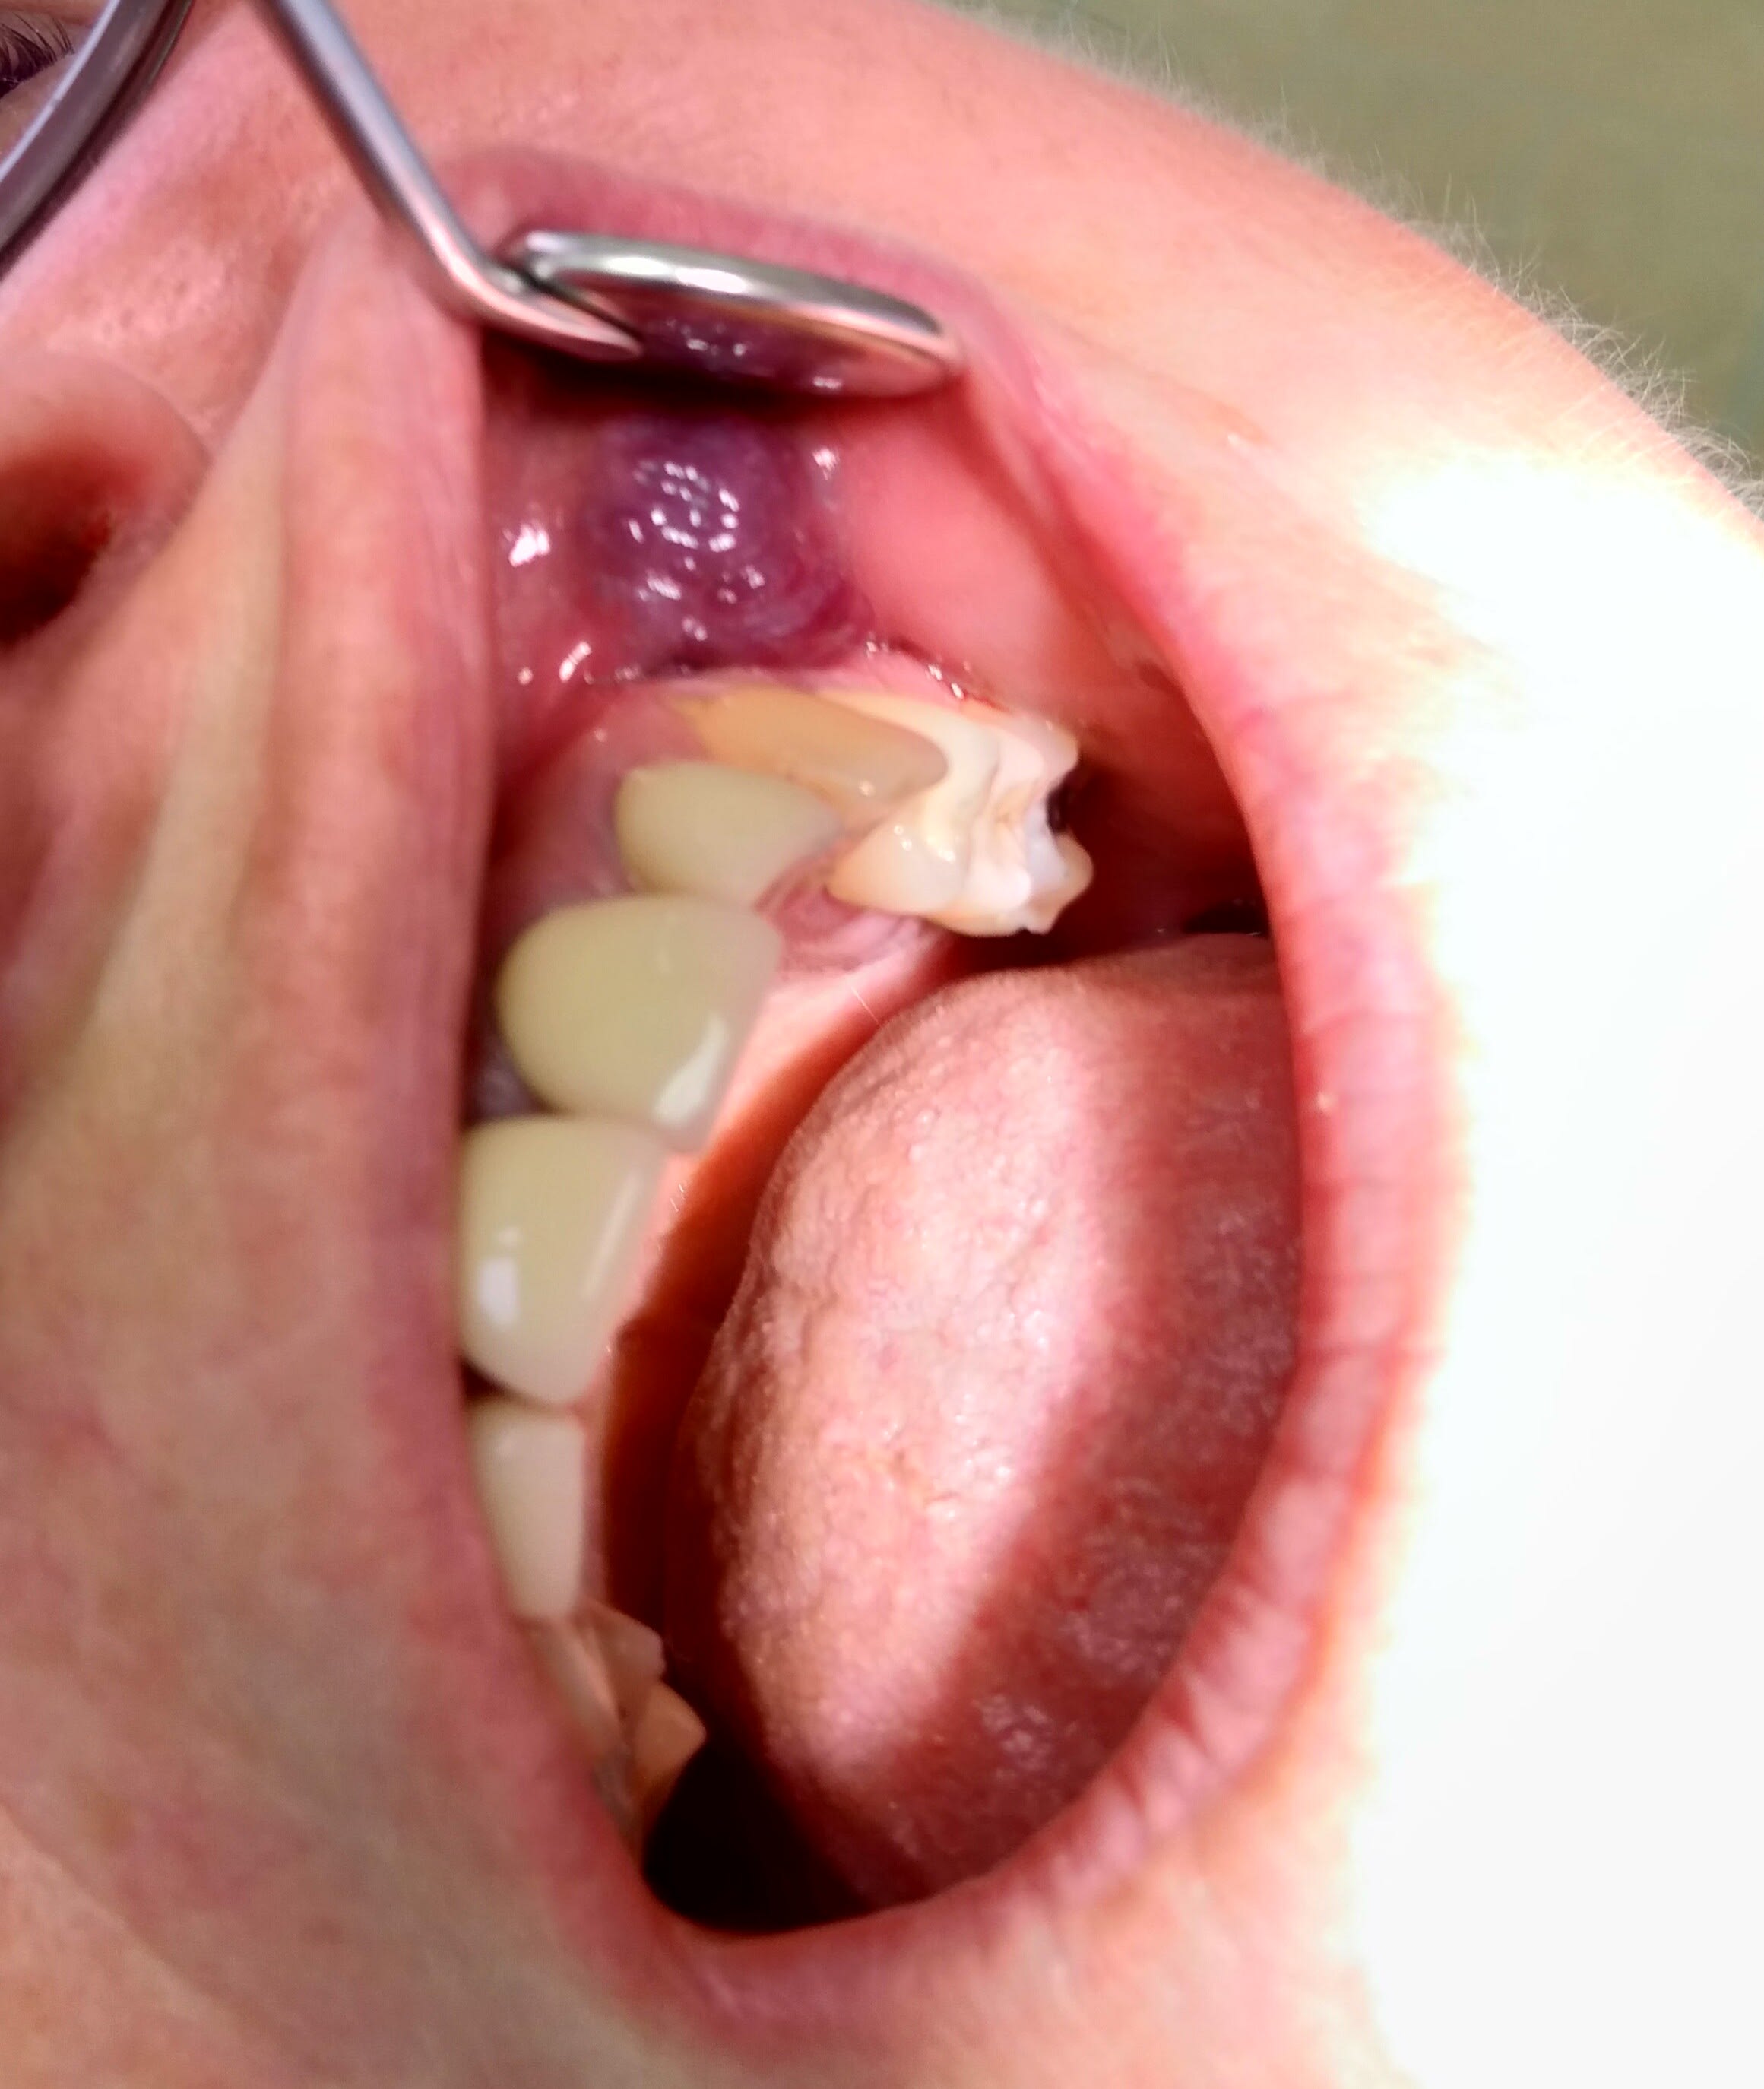

Est-ce que quelqu'un aurait une idée sur l'origine de cette "tâche" au niveau de la muqueuse gingivale?

Ça a toujours été là, et c'est complètement asymptomatique.

Ça s’appelle une tache ethnique

Mais, au vu de la faible teneur en mélanine de la peau de ma patiente, je pensais qu'il y avait peut-être une autre explication.

N'aurait-il pas eu un amalgame sur la dent de lait avant l'émergence de cette dent qui aurait laissé ce tatouage indélébile si on voit bien la tâche tire plus sur le gris que sur le marron qui est caractéristique des tâches ethniques

J'ai eu in peu le même cas